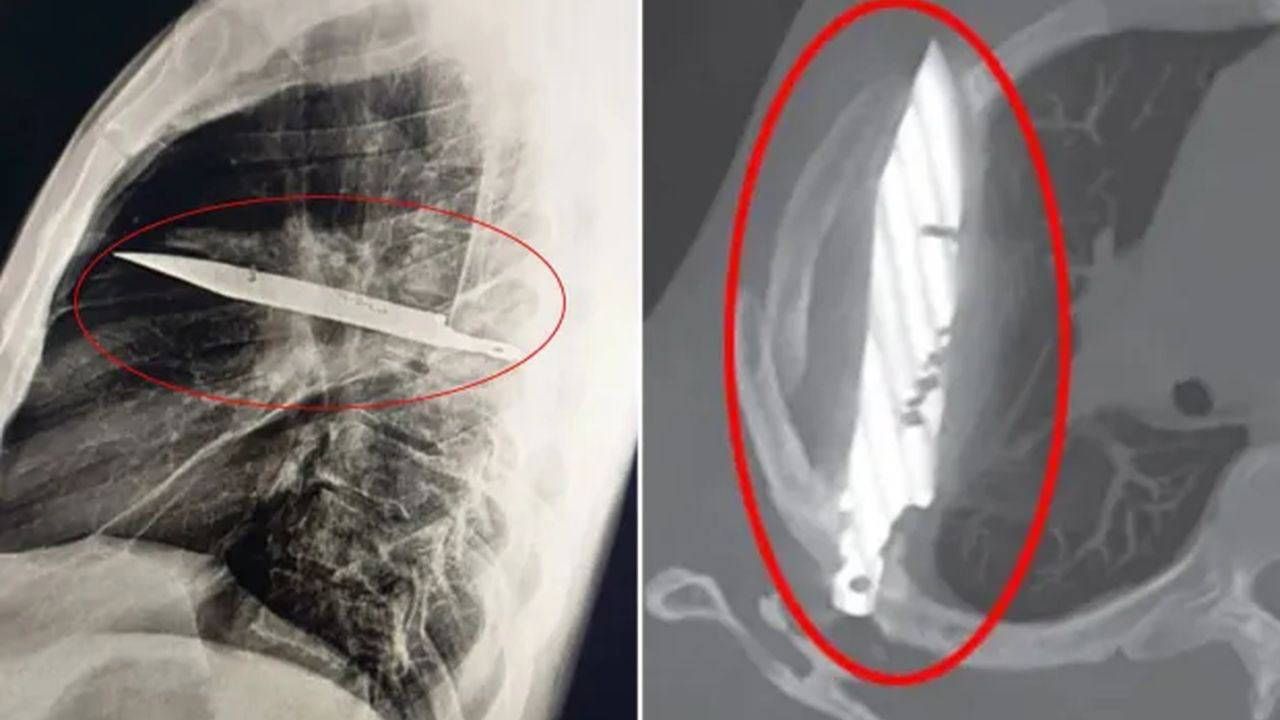

İlk muayenede göğüs röntgeni çekilen hastada, tam 8 yıldır göğüs kafesinde duran büyük bir bıçak bıçağı tespit edildi.

Röntgen sonuçları, bıçağın sağ kürek kemiğinden girip hayati organlara değmeden içeride kaldığını gösterdi.